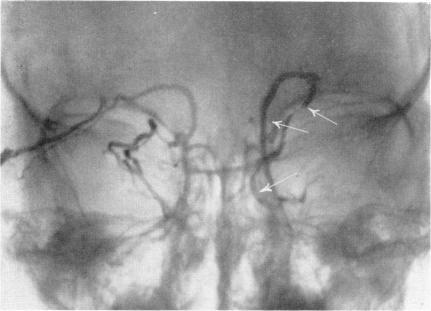

Arteriography and phlebography in the diagnosis of orbital affections.

Bull N Y Acad Med. 1968 Apr;44(4):409-30.